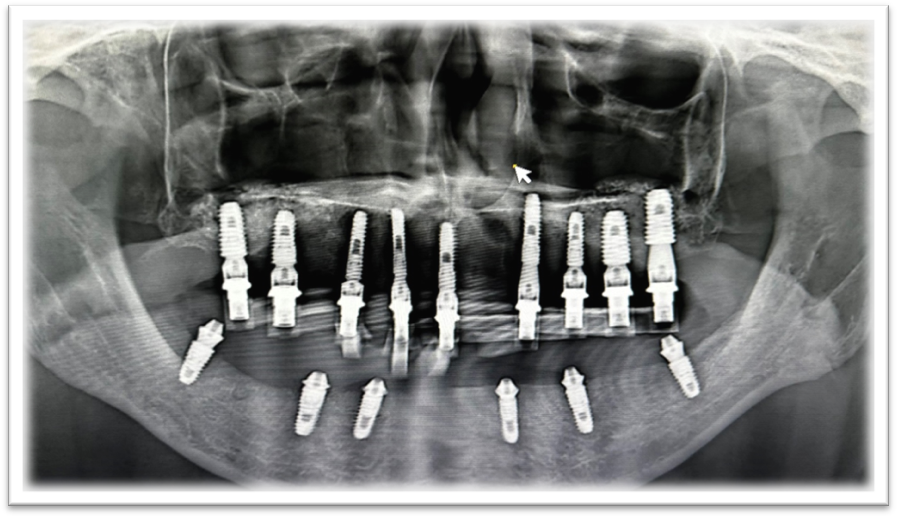

STEP 5: Verification

It is recommended to verify the coded scan body seating using radiographic imaging. Radiographically, you will check that the coded scan bodies are flush with the multi-unit abutment.